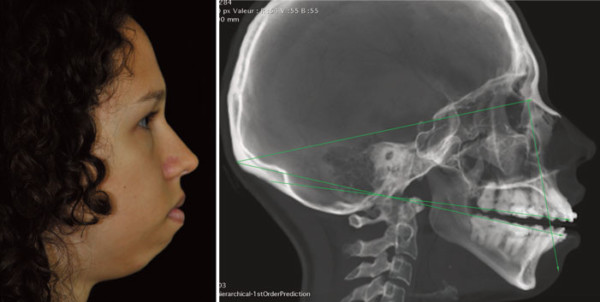

Simulation chirurgie esthétique Avant / Après - Chirurgie Avant Après